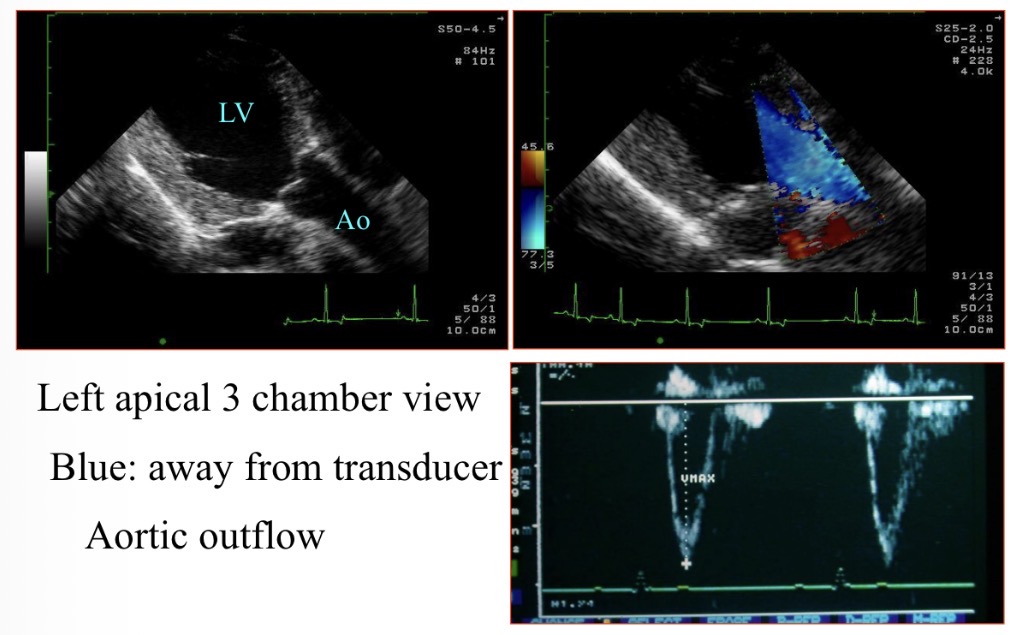

Colour flow Doppler - Blue colour meaning

Away from probe

Why is the blood blue when moving LV → aorta